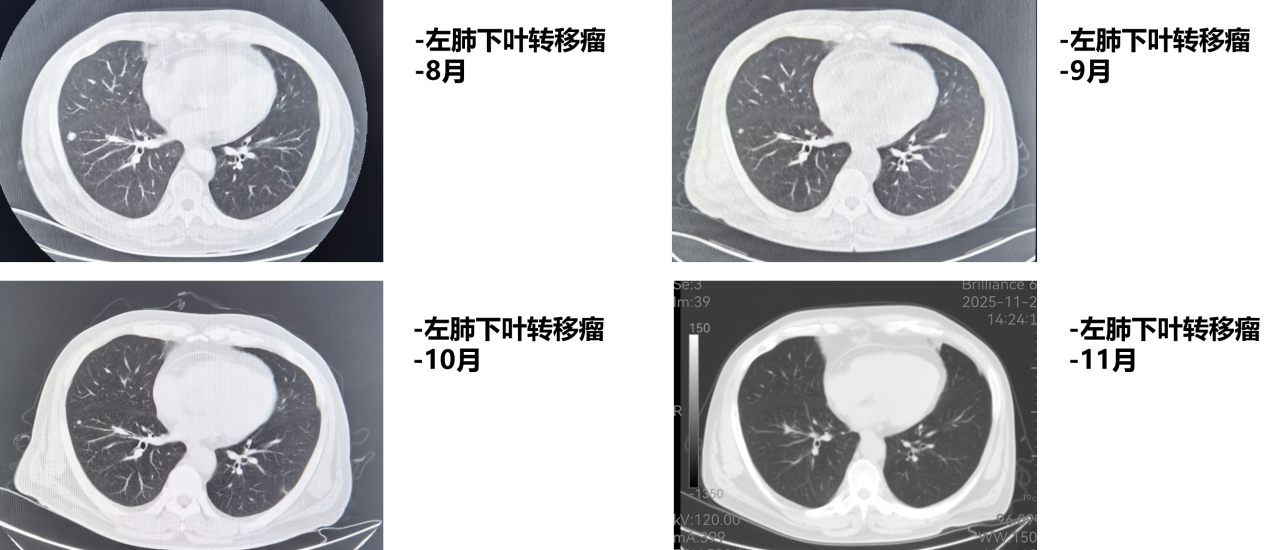

1周期后(2025年9月)复查CT:食管病变、纵隔淋巴结较前减小,双肺转移结节较前部分减小。1周期即显现疗效。

4周期后(2025年11月)复查CT:与2025-10-17日图像对比,食管癌治疗后改变,同前相仿;纵隔淋巴结治疗后改变,较前减小;双肺多发小结节,考虑转移瘤治疗后改变,部分较前略减小。

疗效评估:达到部分缓解(PR)

本例患者PD-L1 CPS评分为3分,属于CheckMate 648研究中获益更为显著的PD-L1阳性人群。经过4个周期纳武利尤单抗联合化疗后,影像学复查显示原发灶及所有转移病灶均明显缩小,疗效评估达PR,与研究中PD-L1阳性患者高达53%的ORR相符。